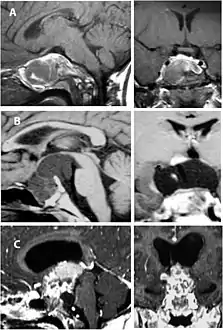

Imaging scans for craniopharyngioma

A physician can conduct a few scans and tests to diagnose a person with craniopharyngioma.[19] High-resolution magnetic resonance imaging (MRI) is commonly used as a diagnostic tool; however, computer tomography (CT) remains the gold standard imaging choice for craniopharyngioma diagnosis as it can detect the severity of the calcification within the tumour.[20]

In some cases, a powerful 3T (Tesla) MRI scanner can help define the location of critical brain structures affected by the tumor. The histologic pattern consists of nesting of squamous epithelium bordered by radially arranged cells. It is frequently accompanied by calcium deposition and may have a microscopic papillary architecture. A computed tomography (CT) scan is also a good diagnostic tool, as it detects calcification in the tumor.[21]

CT scan showing a craniopharyngioma

CT scan showing a craniopharyngioma Enhanced T1 weighted MRIs of craniopharyngiomas

Enhanced T1 weighted MRIs of craniopharyngiomas Micrograph showing the characteristic features of an adamantinomatous craniopharyngioma - cystic spaces, calcifications, and "wet" keratin, HPS stain